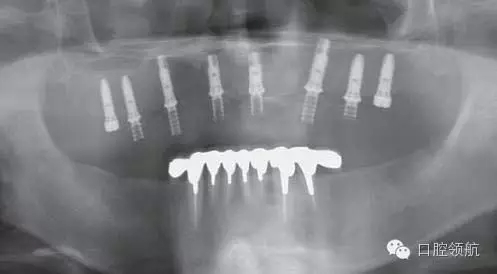

X線影像也未見異常(圖2)。

圖2 X線影像未見異常。